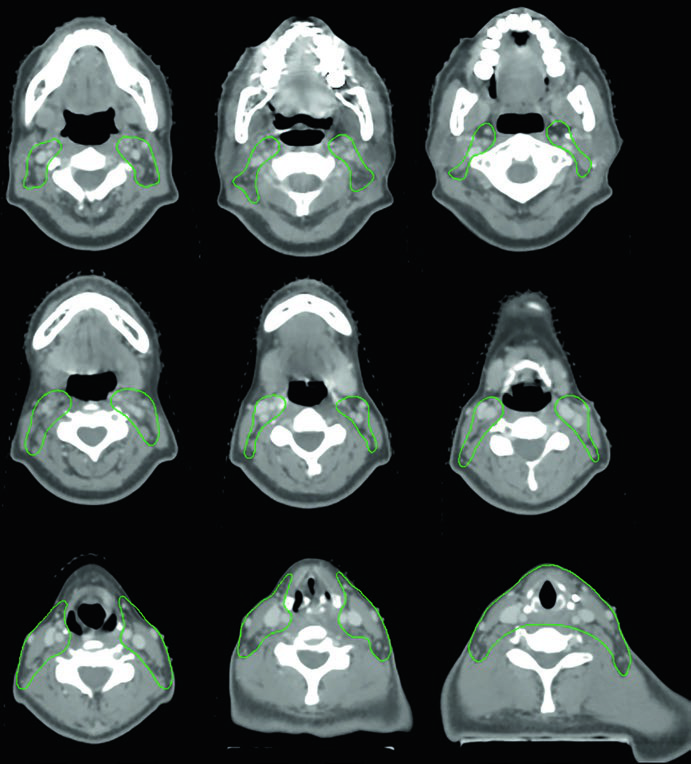

Caso 3 — Anaplásico pós-operatório (Fig. 9.3): Mulher de 50 anos com carcinoma anaplásico submetida a ressecção com extensão extratireoidiana e margens positivas, sem linfonodos envolvidos. Recebeu quimiorradiação pós-operatória. O CTV70 Gy (vermelho) inclui o leito tumoral e os clips cirúrgicos, enquanto o CTV60 Gy (verde) cobre o risco subclínico do compartimento central. A ausência de linfonodos positivos não elimina a necessidade de irradiação subclínica nesse subtipo histológico agressivo — o anaplásico tem taxa de recorrência local e a distância significativamente maior que os diferenciados.

Caso 4 — Recorrência multifocal de variante de células altas (Fig. 9.4): Mulher de 61 anos com variante de células altas do carcinoma papilar, submetida a três cirurgias prévias, que se apresentou com recorrência multifocal. Foi tratada com quimiorradioterapia definitiva. O GTV70 Gy (vermelho) demarca cada foco de recorrência, e o CTV60 Gy (verde) cobre o pescoço subclínico em risco. A variante de células altas é reconhecidamente mais agressiva que a variante papilar clássica, com maior propensão a recorrência e comportamento biologicamente mais adverso.

Quando há recorrência multifocal após múltiplas cirurgias, o campo cirúrgico se torna hostil — fibrose extensa, distorção anatômica e risco aumentado de lesão nervosa tornam nova ressecção proibitivamente arriscada. A quimiorradioterapia definitiva com IMRT permite entregar 70 Gy a cada foco individualmente, com gradiente de dose favorável para os tecidos adjacentes. Cada foco de recorrência exige seu próprio GTV delineado, e o plano precisa acomodar múltiplos alvos de alta dose simultaneamente.